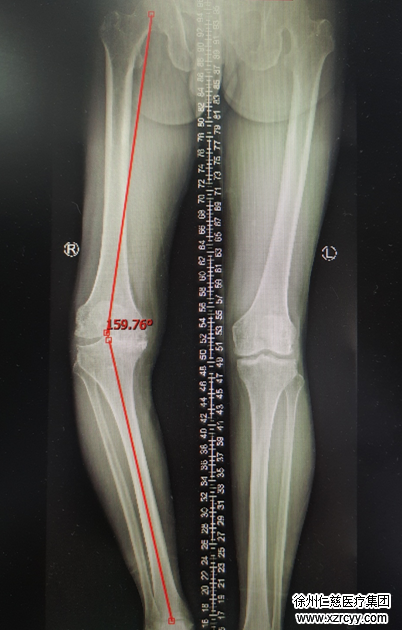

周大爷在关节科作了检查,确诊是右膝关节内翻畸形,骨性关节炎。在充分论证病情、与家属商讨后,关节科蒋守海主任、邱东新组长决定给老人实施导航下人工关节置换手术。术后,周大爷膝关节的畸形得到很好的矫正,在医院恢复的两周时间里,老人已可以下地正常行走,膝关节功能得到明显改善。

术前片

“常规的膝关节置换手术,更依赖术者的经验和目测解剖标志进行,误差难以避免。而通过计算机‘导航’,可以精确到1°,能为患者带来更好的下肢力线和临床疗效。 ”蒋守海主任介绍,计算机导航下的人工膝关节表面置换术,是精准医疗在关节外科的一项标志性技术。与传统膝关节置换手术相比,它可以帮助术者实现精准截骨,更准确的力线纠正,最优化地选择假体,并能更精确地实现软组织平衡。